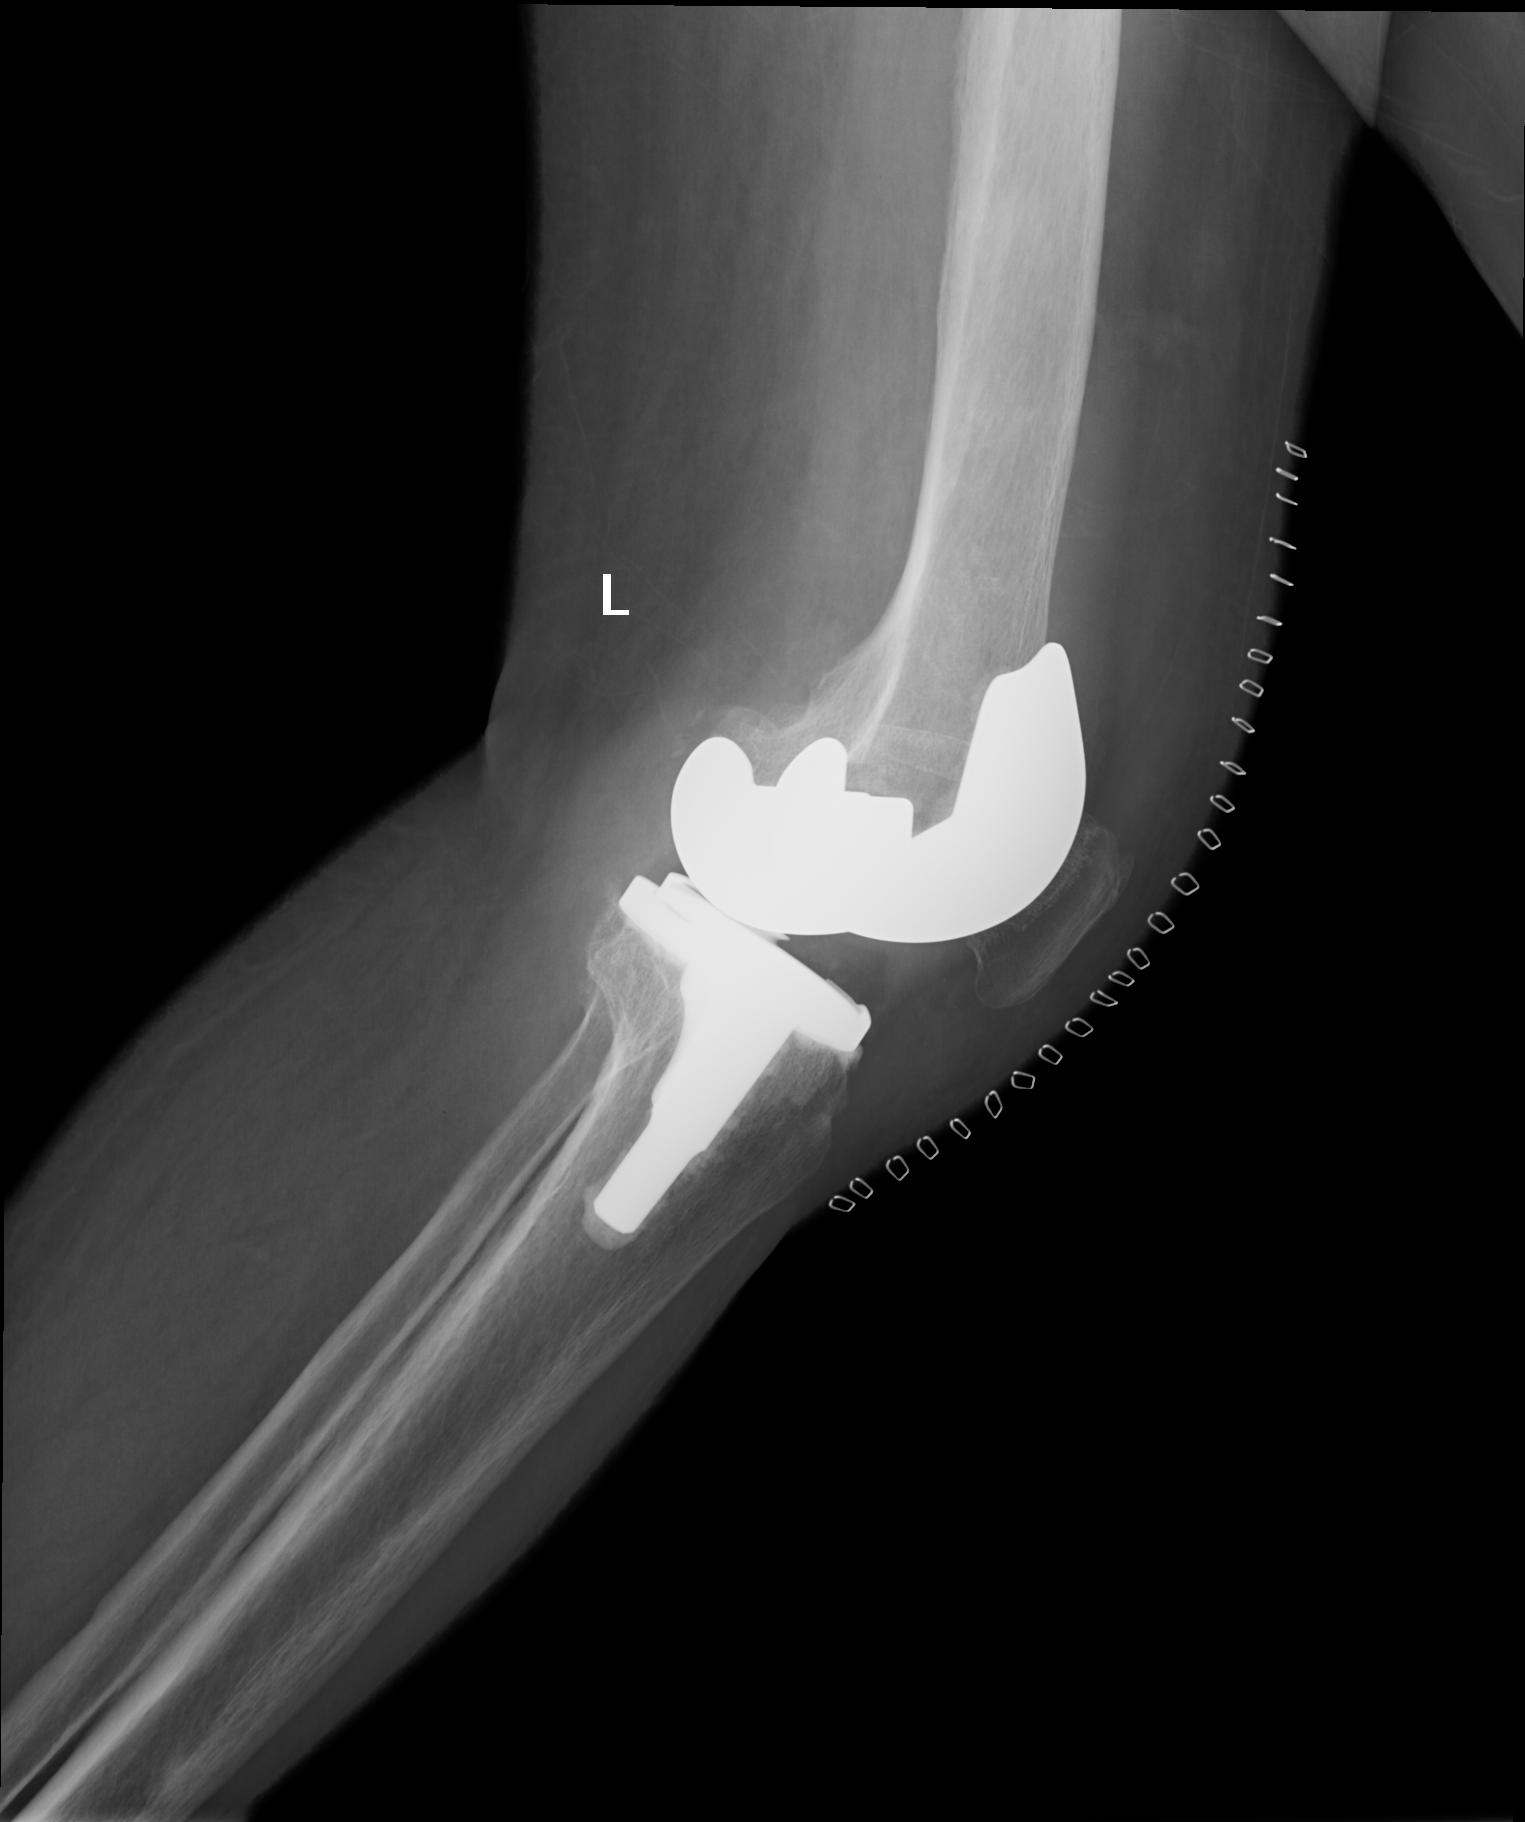

病例一:患者女性,72歲。主因“左膝疼痛伴活動(dòng)受限4年”入院?;颊咝g(shù)前走路時(shí)明顯跛行,連續(xù)行走最多50米需要坐下休息。

患者術(shù)前              患者術(shù)后

患者術(shù)后全長